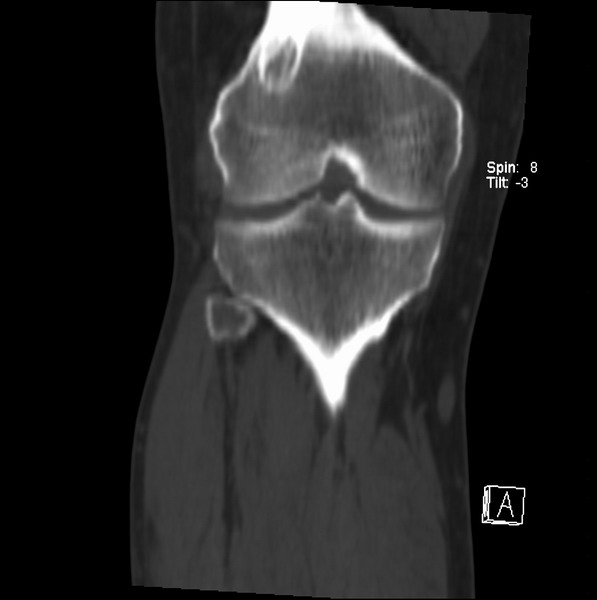

标题: CT21959:骨肿瘤请会诊。

右侧膝关节疼痛一月

男、48

股骨下段、胫骨上段。

1、股骨干骺端病变考虑干骺端纤维性皮质缺损愈后(非骨化性纤维瘤)改变,胫骨近端内生骨瘤(或干骺端纤维性皮质缺损愈后改变);

2、骨关节炎,骨质增生,股骨外侧髁退变性囊肿(关节面软骨下囊肿);

3、髌骨前缘裂纹骨折?

考虑骨样骨瘤

多发内生软骨瘤!

1、股骨干骺端病变考虑干骺端纤维性皮质缺损愈后(非骨化性纤维瘤)改变,胫骨近端内生骨瘤;

股骨干骺端病变考虑非骨化性纤维瘤。

支持非骨化性纤维瘤

非骨化性纤维瘤